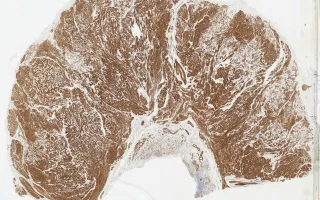

18 year old female with a history of tuberous sclerosis, who presented with blood per rectum and a long history of intestinal pseudo-obstruction. MRI showed asymmetric thickening of the rectum. The patient underwent a proctectomy.

Patients with tuberous sclerosis complex (TSC) are predisposed to a number of tumours, including pulmonary lymphangioleiomyomatosis (LAM) and renal angiomyolipomas (AML). This case is a rare example of leiomyomatosis-like lymphangioleiomyomatosis involving the rectum. Microscopically, the rectal wall is thickened with ill-defined nodules of spindle cells and vessels. LAM and AML are both part of the spectrum of perivascular epithelioid tumours (PEComas). Immunohistochemical stains showed that the lesional cells were diffusely positive for desmin and SMA, and had patchy HMB-45, ER, and PR positivity. This resection specimen also contained an incidental well-differentiated neuroendocrine tumour.

This slide shows H&E stain, see Related Content for HMB-45 and SMA stains.